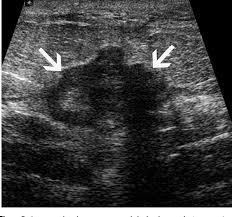

Did not respond to antibiotic and was referred for biopsy. Inflammatory breast cancer is often misdiagnosed because it is so rare, and is difficult to treat because it is particularly aggressive. What does breast cancer look like on a mammogram? However, inflammatory breast cancers are more likely to show solid mass lesions. My last breast ultrasound was december. As these inflammatory breast cancer picture shows, the texture of the breast may change and appear to look dimpled or ridged, like an orange peel. The woman who has inflammatory breast cancer has breast cancer that's red and inflamed, with an angry look to the breast cancer, he says. The problem is that inflammatory breast cancer can look very much like mastitis early on, and is often diagnosed only after a woman has been treated first for mastitis (often with no improvement in symptoms). What does breast cancer look like? I need some knowledge about ibc. These tubes, which are hollow, allow lymph fluid to drain out of the breast. I have inflammatory breast cancer which was firstly diagnosed as mastitis in jan 09. Women or men who develop any of the inflammatory breast cancer early signs should seek medical care immediately to ensure timely treatment.

It's called inflammatory because that's how it looks. Any area that does not look like normal tissue is a possible cause for concern. Inflammatory breast cancer, also known as carcinomatous mastitis, t4d, or pev 2 or 3, is the only real therapeutic emergency in breast oncology, given the high risk of metastasis, the reason for the most unfavourable prognosis of all breast cancers.it must consequently be diagnosed rapidly, and imaging examinations must in no case delay therapeutic management. Because ibc grows quickly, it is usually found at a locally advanced stage, meaning that cancer cells have spread into nearby breast tissue or lymph nodes. A breast ultrasound is a scan that uses penetrating sound waves that do not affect or damage the tissue and cannot be heard by humans. Ultrasound is useful for looking at some breast changes, such as lumps (especially those that can be felt but not seen on a mammogram) or changes in women with dense breast tissue. As these inflammatory breast cancer picture shows, the texture of the breast may change and appear to look dimpled or ridged, like an orange peel. Their differences, however, lie in their enhancement.

These tubes, which are hollow, allow lymph fluid to drain out of the breast. The problem is that inflammatory breast cancer can look very much like mastitis early on, and is often diagnosed only after a woman has been treated first for mastitis (often with no improvement in symptoms). Kathleen ruddy inflammatory breast cancer accounts for approximately 5% of all cases of invasive breast cancer in the united states. Inflammatory breast cancer is often misdiagnosed because it is so rare, and is difficult to treat because it is particularly aggressive. A small red spot that looks very much like an insect bite or rash can be an early sign of ibc. Because ibc grows quickly, it is usually found at a locally advanced stage, meaning that cancer cells have spread into nearby breast tissue or lymph nodes. Googled and freaking out about ibc. The woman who has inflammatory breast cancer has breast cancer that's red and inflamed, with an angry look to the breast cancer, he says. Online says it develops suddenly. However, these signs and symptoms are most often associated with benign breast conditions. Inflammatory breast cancer (ibc) is rare, making up about 2 to 4 percent of breast cancer cases. Other ultrasound findings that suggest breast cancer include: The breast tissue deflects these waves causing echoes, which a computer uses to paint a picture of what's going on inside the breast tissue (no radiation is involved).

However, inflammatory breast cancers are more likely to show solid mass lesions. The problem is that inflammatory breast cancer can look very much like mastitis early on, and is often diagnosed only after a woman has been treated first for mastitis (often with no improvement in symptoms). This condition usually does not develop a lump, but commonly affects the breast skin. The aim of this study was to evaluate the features of inflammatory breast carcinoma (ibc) on mri compared with mammography and ultrasound and to better define the role of mri in patients with this aggressive disease. These tubes, which are hollow, allow lymph fluid to drain out of the breast.